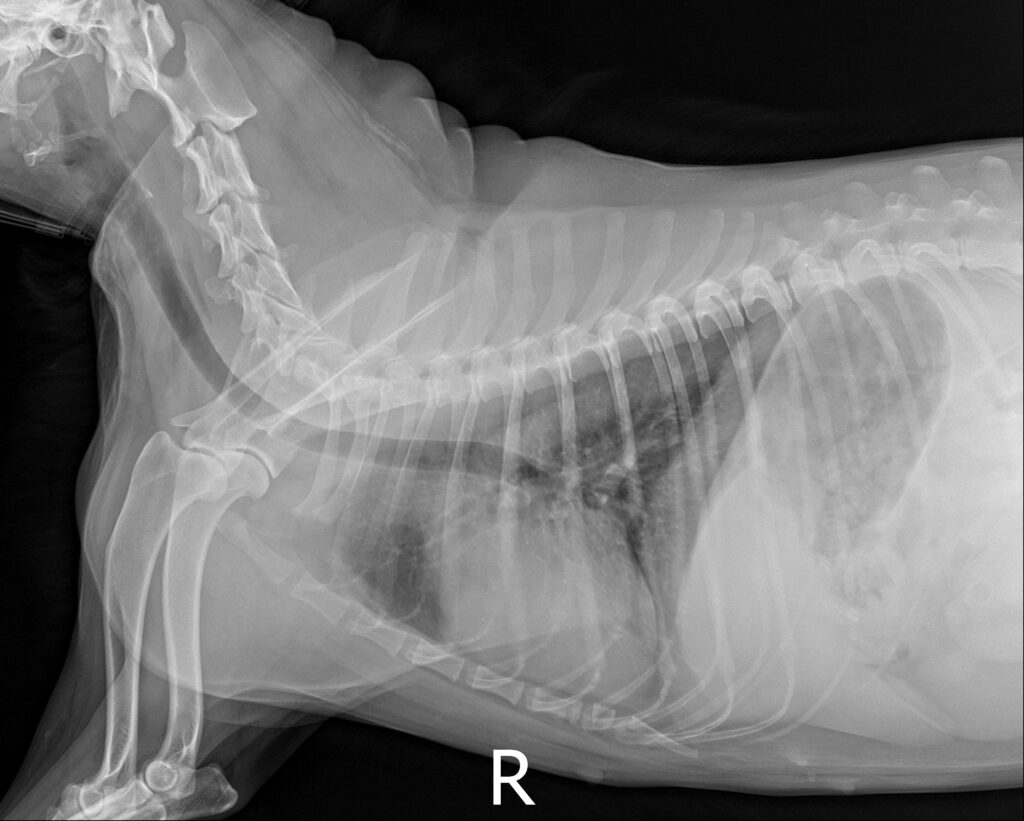

복부 방사선 검사 결과 / 출처: 24시온숲동물의료센터

복부초음파·방사선검사 결과

- 내원 당시 시행한 복부 초음파 및 방사선 검사에서 정상적으로는 4mm 정도 두께인 자궁이 약 4cm까지 심하게 확장되어 있는 모습이 확인되었습니다. 내부에는 고름으로 추정되는 내용물이 가득 차 있었으며, 이는 전형적인 자궁축농증의 소견에 해당합니다.